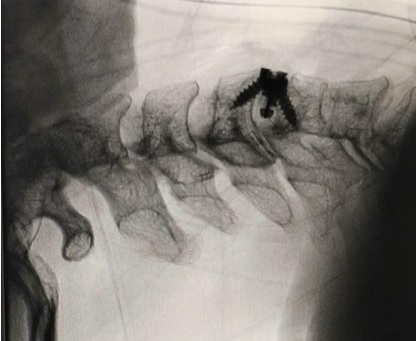

Ca phẫu thuật diễn ra an toàn, thuận lợi. Dưới hỗ trợ của hệ thống C-arm trong mổ, kính vi phẫu phóng đại, ê-kíp kiểm tra chính xác vị trí phẫu thuật và dụng cụ cố định. Sau mổ, người bệnh hồi phục tốt: sau 5 ngày, triệu chứng đau cổ và tê bì hai tay giảm rõ rệt, chức năng vận động cải thiện, người bệnh được xuất viện trong tình trạng ổn định.

Hình ảnh chụp C-arm cột sống cổ sau phẫu thuật ACDF tầng C4–C5